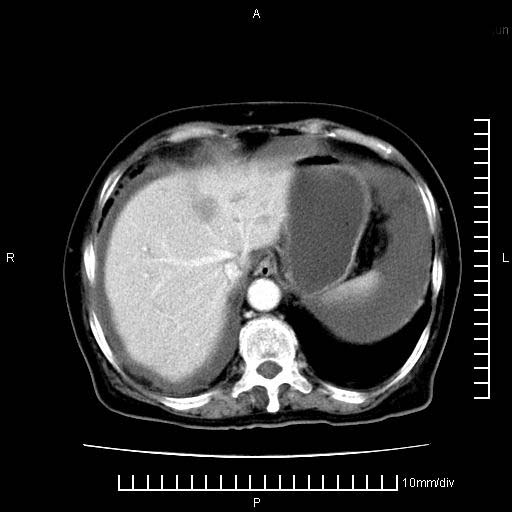

标题: CT28280:腹部增强:女性,80岁

上腹疼痛月余,外院核磁诊断胰腺癌。现临床示右下腹可明显触及包块,可片子上怎么没有看到?

1。胰腺ca伴腹膜腔转移

2。肝左叶低密度灶,考虑转移可能

支持胰腺癌肝内转移,腹水改变。

1、考虑胰腺癌伴腹膜腔转移,胸腹水。

2、肝脏转移可能。

1)考虑胰腺癌并胰腺假性囊肿形成。2)肝内低密度灶,不排除转移。3)右肾盂积水。4)腹水。5)右侧胸腔积液并右肺下叶部分膨胀不全。

考虑胰腺ca伴腹膜腔转移、肝左叶转移、右肾积水。右胸腔积液。